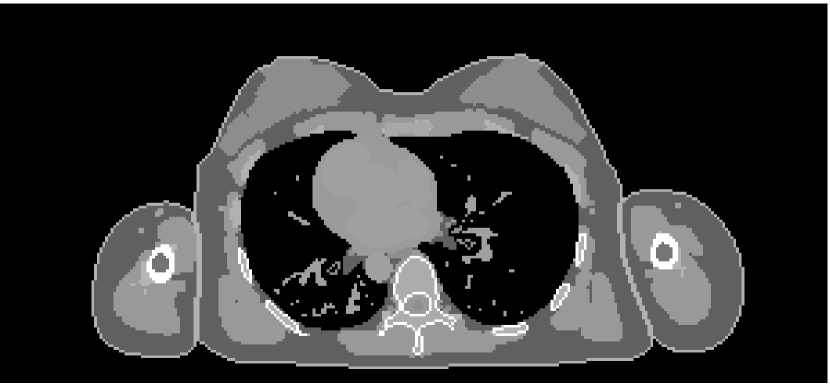

The results from our reconstruction test are illustrated in Figure 9 and Table 3.

Refer to caption

(a) FBP chest

(b) FBP pelvis

(c) PWLS chest

(d) PWLS pelvis

(e) Poly-SIR chest

(f) Poly-SIR pelvis

(g) IMPACT chest

(h) IMPACT pelvis

(i) Polyquant chest

(j) Polyquant pelvis

Figure 9: Results from electron density reconstruction test for chest and pelvis fan-beam data with display window [0.8,1.2] to aid visualisation of soft tissue and reconstruction artefacts

chest datapelvis dataSchemeρe RMSEρ RMSEρe RMSEρ RMSEFBP0.1360.1400.2010.226PWLS0.03890.04260.1330.166Poly-SIR0.03630.03850.08390.101IMPACT0.03070.03260.1330.159Polyquant0.02980.03160.05130.0746missing-subexpressionmissing-subexpressionmissing-subexpressionmissing-subexpressionmissing-subexpressionmissing-subexpressionchest datapelvis datamissing-subexpressionmissing-subexpressionmissing-subexpressionmissing-subexpressionmissing-subexpressionSchemesubscript𝜌𝑒 RMSE𝜌 RMSEsubscript𝜌𝑒 RMSE𝜌 RMSEmissing-subexpressionmissing-subexpressionmissing-subexpressionmissing-subexpressionmissing-subexpressionFBP0.1360.1400.2010.226PWLS0.03890.04260.1330.166Poly-SIR0.03630.03850.08390.101IMPACT0.03070.03260.1330.159Polyquant0.02980.03160.05130.0746\begin{array}[]{c|c|c|c|c|}\cline{2-5}\cr&\lx@intercol\hfil\text{chest data}\hfil\lx@intercol&\vrule\lx@intercol\hfil\text{pelvis data}\hfil\lx@intercol\vrule\lx@intercol\\ \cline{2-5}\cr\text{Scheme}&\rho_{e}\text{ RMSE}&\rho\text{ RMSE}&\rho_{e}\text{ RMSE}&\rho\text{ RMSE}\\ \hline\cr\text{FBP}&0.136&0.140&0.201&0.226\\ \text{PWLS}&0.0389&0.0426&0.133&0.166\\ \text{Poly-SIR}&0.0363&0.0385&0.0839&0.101\\ \text{IMPACT}&0.0307&0.0326&0.133&0.159\\ \text{Polyquant}&\mathbf{0.0298}&\mathbf{0.0316}&\mathbf{0.0513}&\mathbf{0.0746}\\ \hline\cr\end{array}

In terms of both electron density and mass density accuracy, our proposed method is the best performing method under test. The lack in estimation accuracy in using the water–bone model with Poly-SIR is likely to be due to discrepancies in adipose and spongy bone tissues from water, which were illustrated in Figure 5. We note that Poly-SIR is second best performing in the pelvis case, but it was provided with oracle information on the implant and hard bone, which would be difficult to segment in practice from a preliminary reconstruction such as FBP due to its high noise. IMPACT is understandably very closely performing to our method in the chest case, as these performed similarly in the model test, but the advantage of fitting at each energy is clear in the case of the metal implant, where the IMPACT performance is similar to that of PWLS.